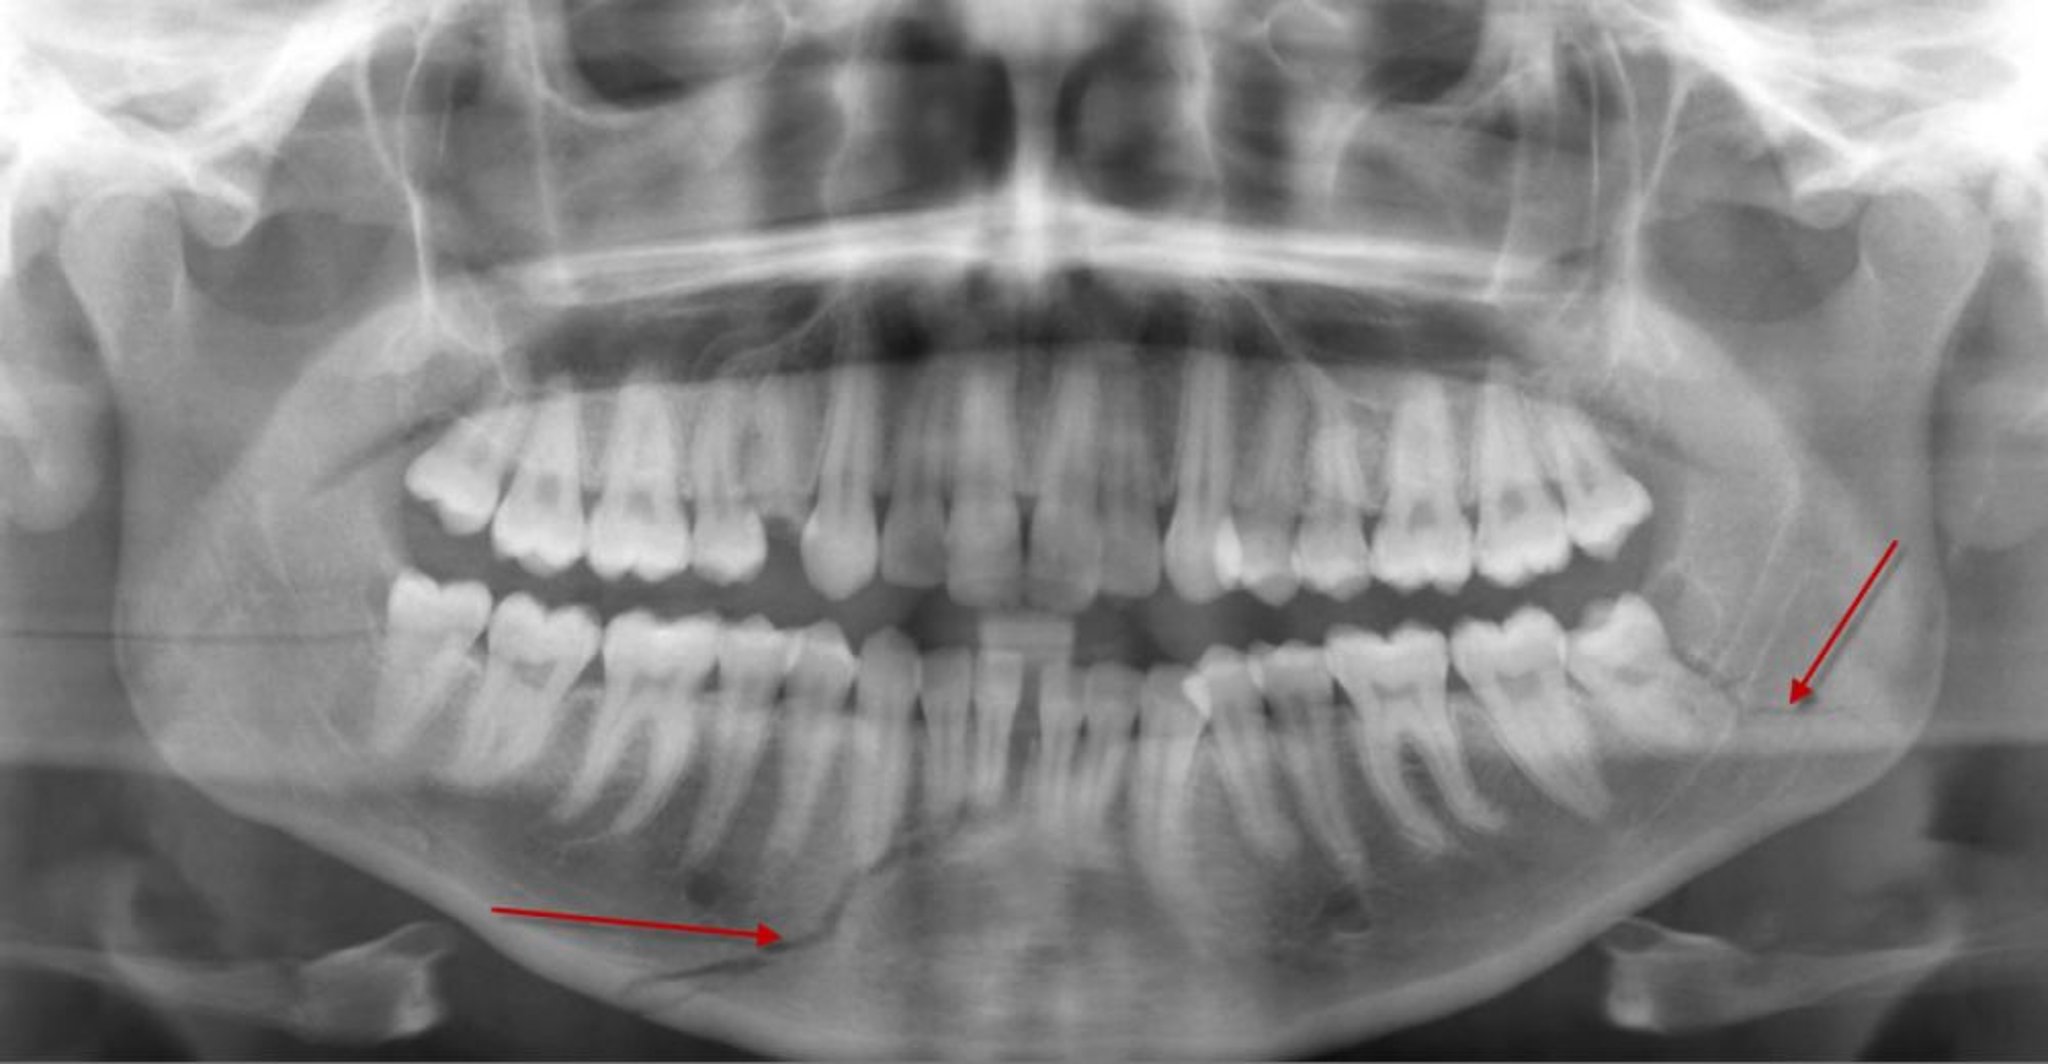

下顎骨骨体部の骨折

このパノラマX線写真では,下顎骨骨体部に骨折を示す透亮像(下の矢印)がみられ,下顎前歯の歯根にまで達している。左下顎角の骨折(矢印)もみられる。